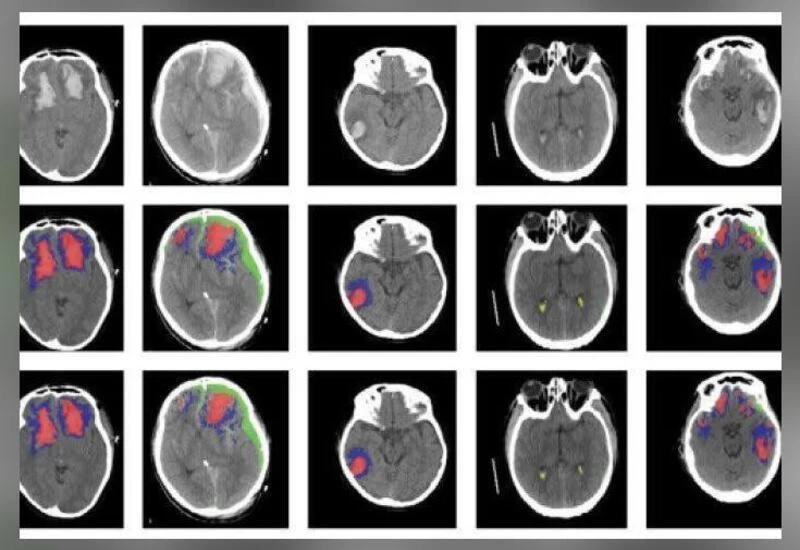

The system is based on an artificial neural network developed at Imperial. The researchers trained the tool on more than 600 CT scans showing different types of brain lesions. They then checked if it worked by applying it to an existing dataset of scans.

They found that the AI successfully classified individual parts of each image — and worked out whether the brains were damaged or not.